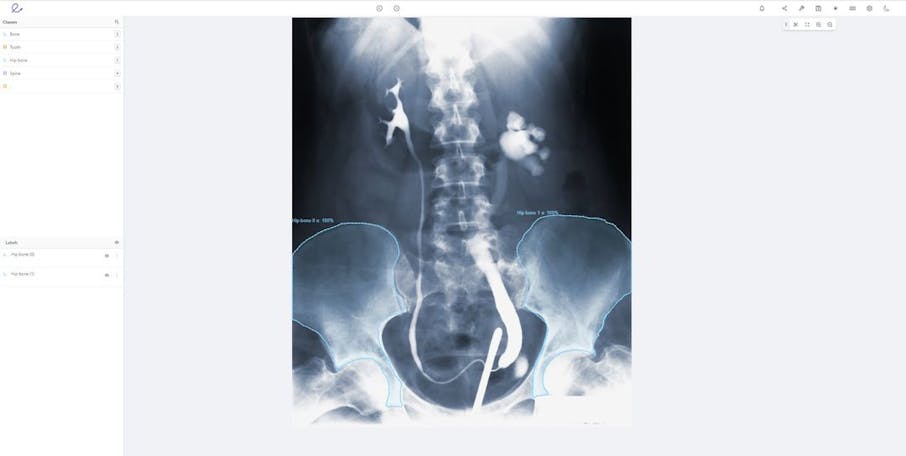

Automated annotation of DICOM images

DICOM support in Encord